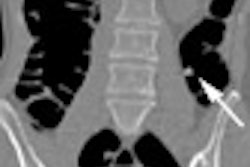

The researchers reviewed a series of scans for lesions containing contrast that had penetrated into the coronary artery wall and that were surrounded by plaque, according to the abstract for their poster presentation. Extraluminal densities appeared on 22% (39/176) of the contrast-enhanced scans.

Fourteen of the 30 patients had calcium that explained the density; another nine cases were equivocal. But 4% (7/176) of the study patients showed no calcium on the unenhanced scan, which led the researchers, by process of elimination, to a diagnosis of plaque rupture.